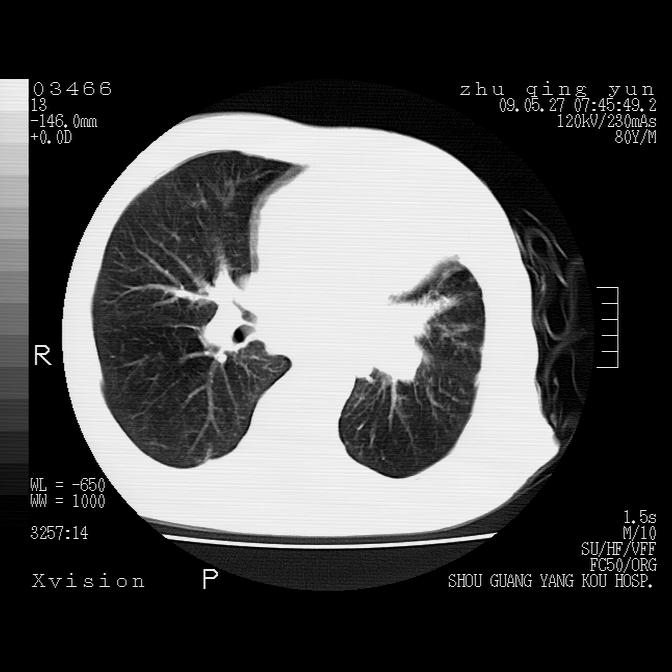

1)考虑左肺中央型肺癌并阻塞性肺炎,后下纵隔受侵伴纵隔淋巴结转移。2)双侧少量胸腔积液,胸膜增厚。3)心包积液。

左肺下叶见多发片状及结节状病灶,左肺基底段支气管闭塞,纵隔内见多发淋巴结肿大,纵隔向左侧移位,左侧胸廓变小。应该是左肺下叶中心型肺癌,纵隔淋巴结转移,左侧肺内转移,左肺基底段肺不张,阻塞性肺炎。

1)考虑左肺中央型肺癌并左肺下叶阻塞性肺炎、不张;左胸膜腔积液、心包积液、纵隔淋巴结转移;癌肿累及左心房。2)左心室大。冠状动脉壁钙化斑。

支持以上,左肺肿块应该是周围型吧,考虑左下肺周围型肺癌伴肺内转移,阻塞性肺炎,纵隔淋巴转移,左侧胸膜及心包转移

考虑左下肺中心性肺癌伴阻塞性肺炎,纵隔淋巴转移,左侧胸膜及心包转移。